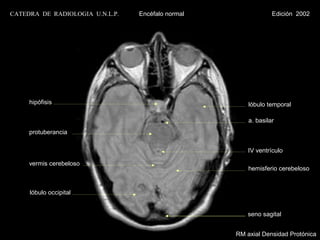

CATEDRA DE RADIOLOGIA U.N.L.P.   Encéfalo normal                Edición 2002

seno esfenoidal

lóbulo temporal                                    a. carótida interna

a. basilar

protuberancia

pedúnculo cerebeloso

medio

vermis cerebeloso

hemisferio cerebeloso

RM axial Densidad Protónica